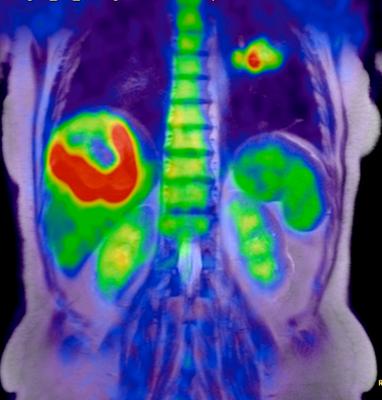

Decades of significant advances and improvements in positron emission tomography (PET) imaging technology have led to the detection of an enzyme in humans that plays a significant role in DNA formation, the building blocks of life. The enzyme, called deoxycytidine kinase (dCK), was previously found to be highly expressed in acute leukemia cells and in activated lymphocytes and controls a critical step in the nucleoside salvage pathway, an important therapeutic and PET imaging target in cancer.

In a seven-year study, a team of UCLA researchers led by Caius Radu, M.D., a UCLA Jonsson Comprehensive Cancer Center member and a professor in the Department of Molecular and Medical Pharmacology, developed a highly sophisticated PET probe called [18F]CFA that is capable of detecting dCK activity in humans for the first time.

"The quality of the images is much better," said Radu. "We are able to clearly see tissues, including tumor tissues, with high dCK activity that we haven't seen before in humans using any of the other probes previously developed for this enzyme."

PET is a noninvasive imaging technology that uses a radioactive substance, called PET probe, to look for disease in the body and it also shows how organs and tissues are functioning. Until recently, PET technology was only able to clearly detect dCK in mice due to metabolic instability of the previous probes and cross-reactivity with a dCK-related enzyme in humans.